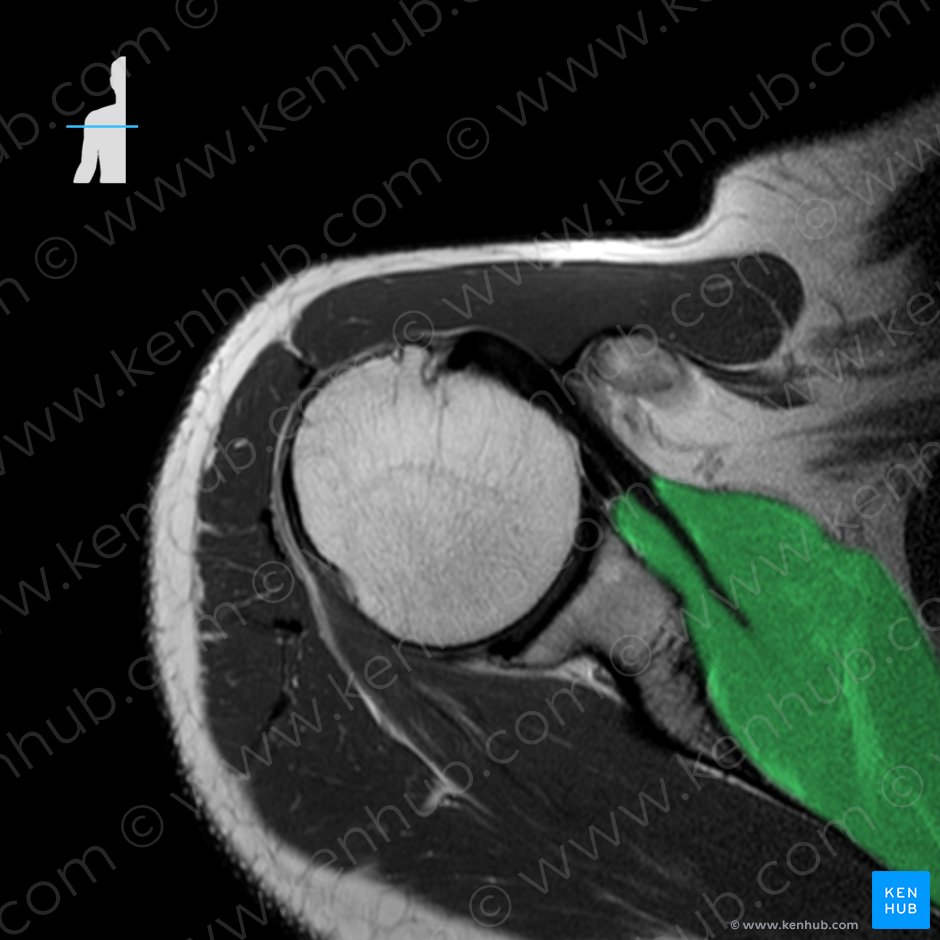

1. 극하근(Infraspinatus, 가시아래근)

origin : 견갑골 극하와의 내측 2/3

Infraspinous fossa of scapula

insertion : 상완골의 대결절

Greater tubercle of humerus

function : Shoulder joint: Arm external rotation;

Stabilizes humeral head in glenoid cavity

극하근은 어깨를 외회전 시키는 근육으로,

어깨통증 시 주로 긴장, 단축되어 운동을 제한시킵니다.

손을 허리 뒤로 올리는데 어려움이 생기고

(*Mouth Wrap-around test)

어깨 뒤, 외측으로 통증이 있어 옆으로 누워 자기 어렵게 됩니다.

극하근 그 자체가 문제여서 통증이 오는 경우보다는,

어깨통증 때 루틴하게 풀어주면 도움이 되는 근육입니다.

촉진 시 견갑골 위, 견갑극 아래쪽에 전체적으로 부착하는 근육이 극하근입니다.

경계를 꼼꼼히 촉진해야 치료 시 기흉을 예방할 수 있습니다.

대부분 어디를 누르던지 통증이 있기 때문에,

가장 큰 압통점을 찾는 것이 포인트며,

건 부착부보다는 근복부의 긴장을 타겟으로 해서 치료합니다.

깊이는 3-4cm, 뼈까지 자입해도 괜찮습니다.

극하근(Infraspinatus)의 연관통(Referred pain)은

어깨관절 깊은곳, 상완 전외측, 전완 외측, 손의 바깥쪽으로 발생합니다.

어깨앞 깊숙한 곳에서 격렬한 통증으로 나타납니다.

종종 견갑골 내측(Scpular medial border)에서 통증이 발생하는 경우도 있습니다.

극하근건염 시 삼각근(deltoid m.) 부분뿐 아니라 손목까지도 통증 방사됩니다.

방사통이 손목까지 오는 회전근개 근육은 극하근과 견갑하근으로

극하근은 deep, 견갑하근은 superficial 한 통증이 있다고 하지만,

손목에 띠를 두른 듯한 통증이 있는 경우 두 근육 모두 치료하는 것이 효과적입니다.